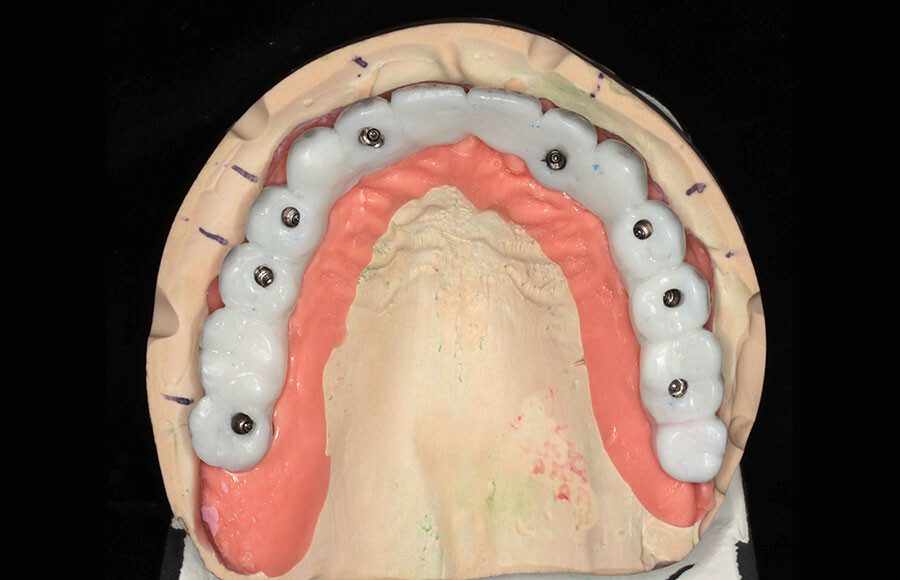

Prototype wax-up, frontal. Any imperfections or patient requests are changed in this prototype stage.

Right transition. We photograph the “transition” from prototype to gums in the event there have been changes since the final impression. Sweat every detail!